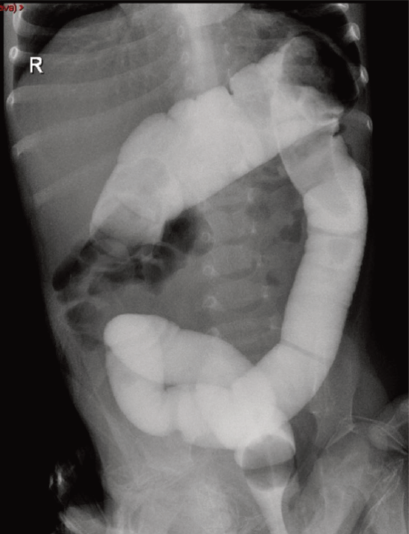

Figura 3 Colon por enema: se observa el paso del medio de contraste hidrosoluble hasta el ángulo hepático